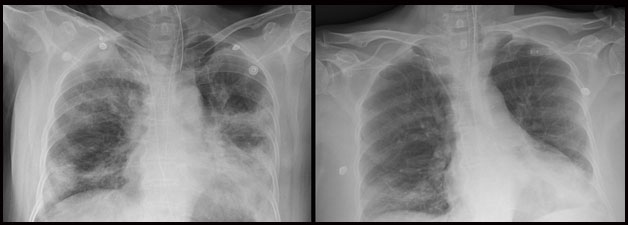

7일 세브란스병원에 따르면 최준용·김신영 교수팀은 코로나19로 위중한 71세 남성과 67세 여성 환자에게 혈장치료를 시행했다. 두 사람 모두 코로나19 폐렴으로 인해 급성호흡곤란증후군이 동반돼 인공호흡기를 단 상태였다.

의료진은 두 환자에게 완치자의 혈장 500㎖를 2회 용량으로 나눠 12시간 간격으로 투여하고 스테로이드 치료를 병행했다. 이후 두 사람 모두 인공호흡기를 뗄 정도로 상태가 호전됐고, 코로나19 검사에서도 음성 판정을 받았다.

최준용 세브란스병원 감염내과 교수는 "두 환자 모두 회복기 혈장 투여와 스테로이드 치료 후 염증 수치, 림프구수 등 각종 임상 수치가 좋아졌다"고 말했다.